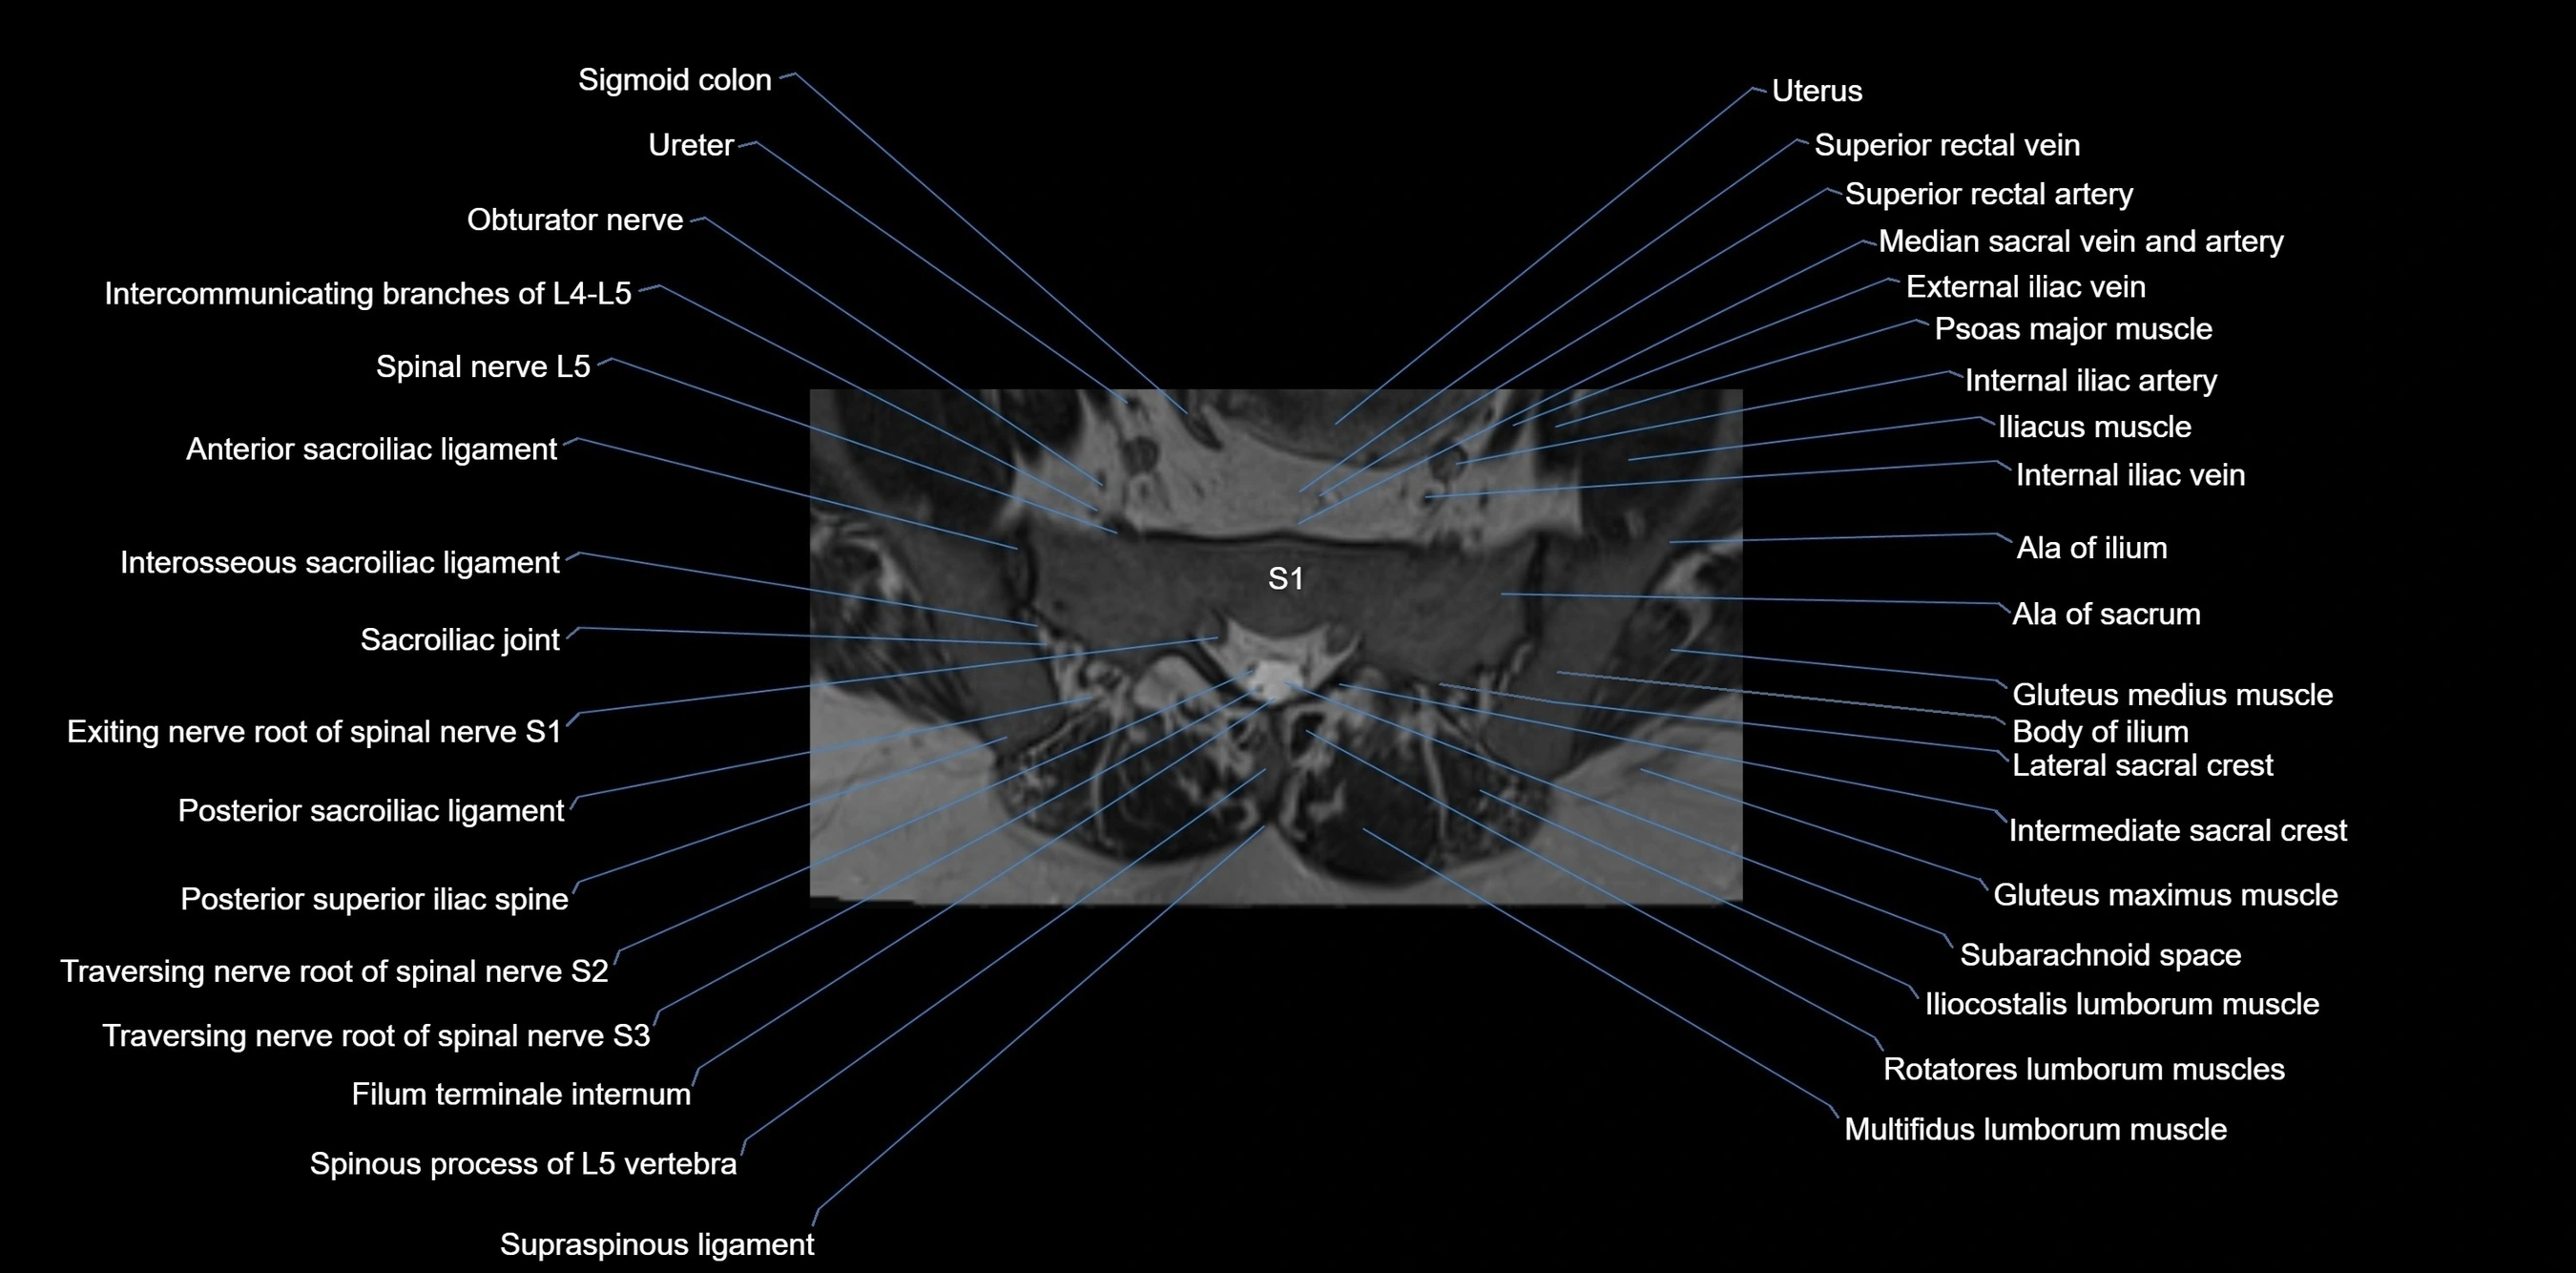

CT VRT image

image